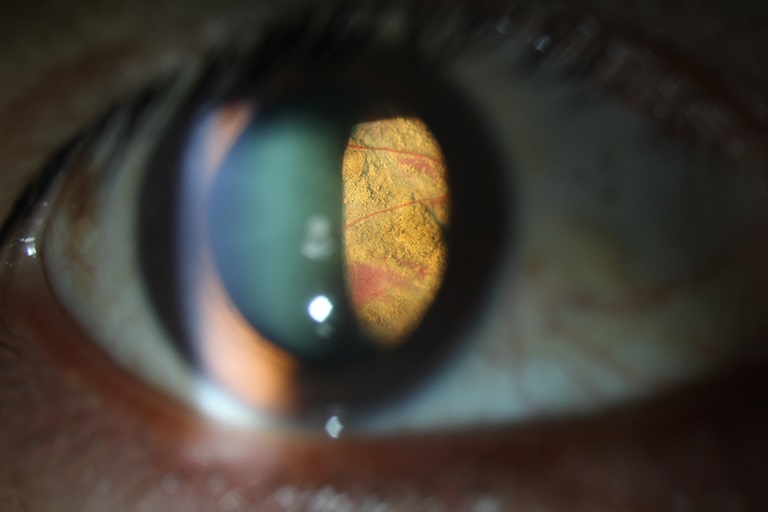

Choroidal Melanoma (ANTERIOR)

Presented by Jason Calhoun, COAThis photograph received Honorable Mention in the category "Slit Lamp Photography" and was displayed at the 2024 ASCRS/OPS Society Exhibit.